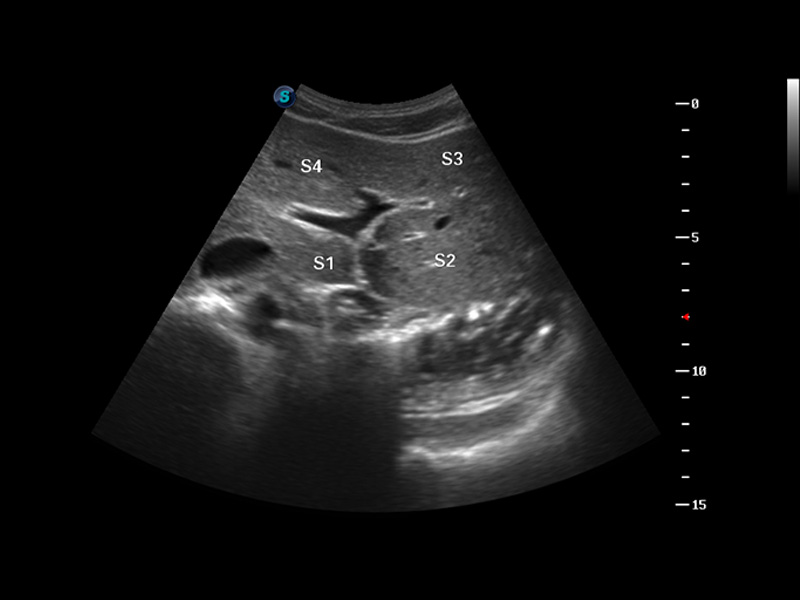

S8 EXP便携式彩色多普勒超声诊断仪是云顶集团官网研发的高端全身应用型便携彩超。高通道的VIS平台融合可视化(Visual)、智能化(Intelligent)和人性化(Smart)的特点,配以云顶集团官网自主研发生产的探头大家族,使您能够快速、准确的获得病人信息,提高工作效率的同时减轻疲劳。

μ-Scan微米成像

谐波成像

空间复合成像